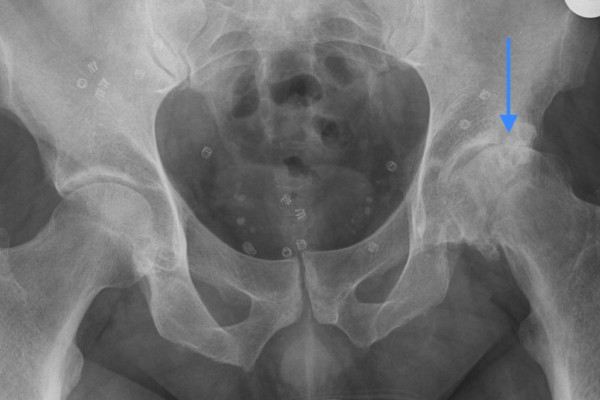

Schwere Arthrose der Linken Hüfte

Abb. 2: Schwere Arthrose der Linken Hüfte (Pfeil), während die rechte Hüfte noch normal ist.